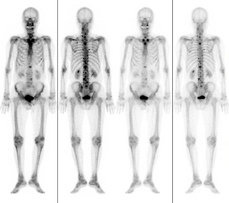

RI検査とはラジオアイソトープ検査の略称です。ラジオアイソトープとは放射線を出す元素である放射性同位元素のことで、RI検査では微量の放射性同位元素を標識した薬剤(放射性医薬品)を体内に投与して行います。

体内に入った薬剤は全身を巡って特定の臓器に集まります。臓器に集まった放射性同位元素から放射線がより多く出てきます。この放射線をガンマカメラといわれる特殊な装置で測定し、集積や分布を画像化します。画像を得ることにより臓器の働き(代謝や機能等)を知ることが出来ます。